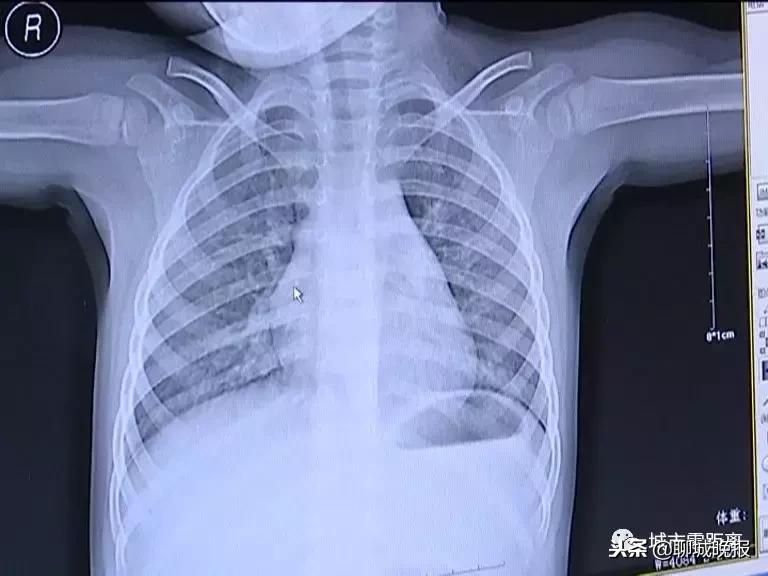

医生通过观察女童肺部的X光片发现

引起女童反复高烧的原因

是细菌感染引起的肺部炎症